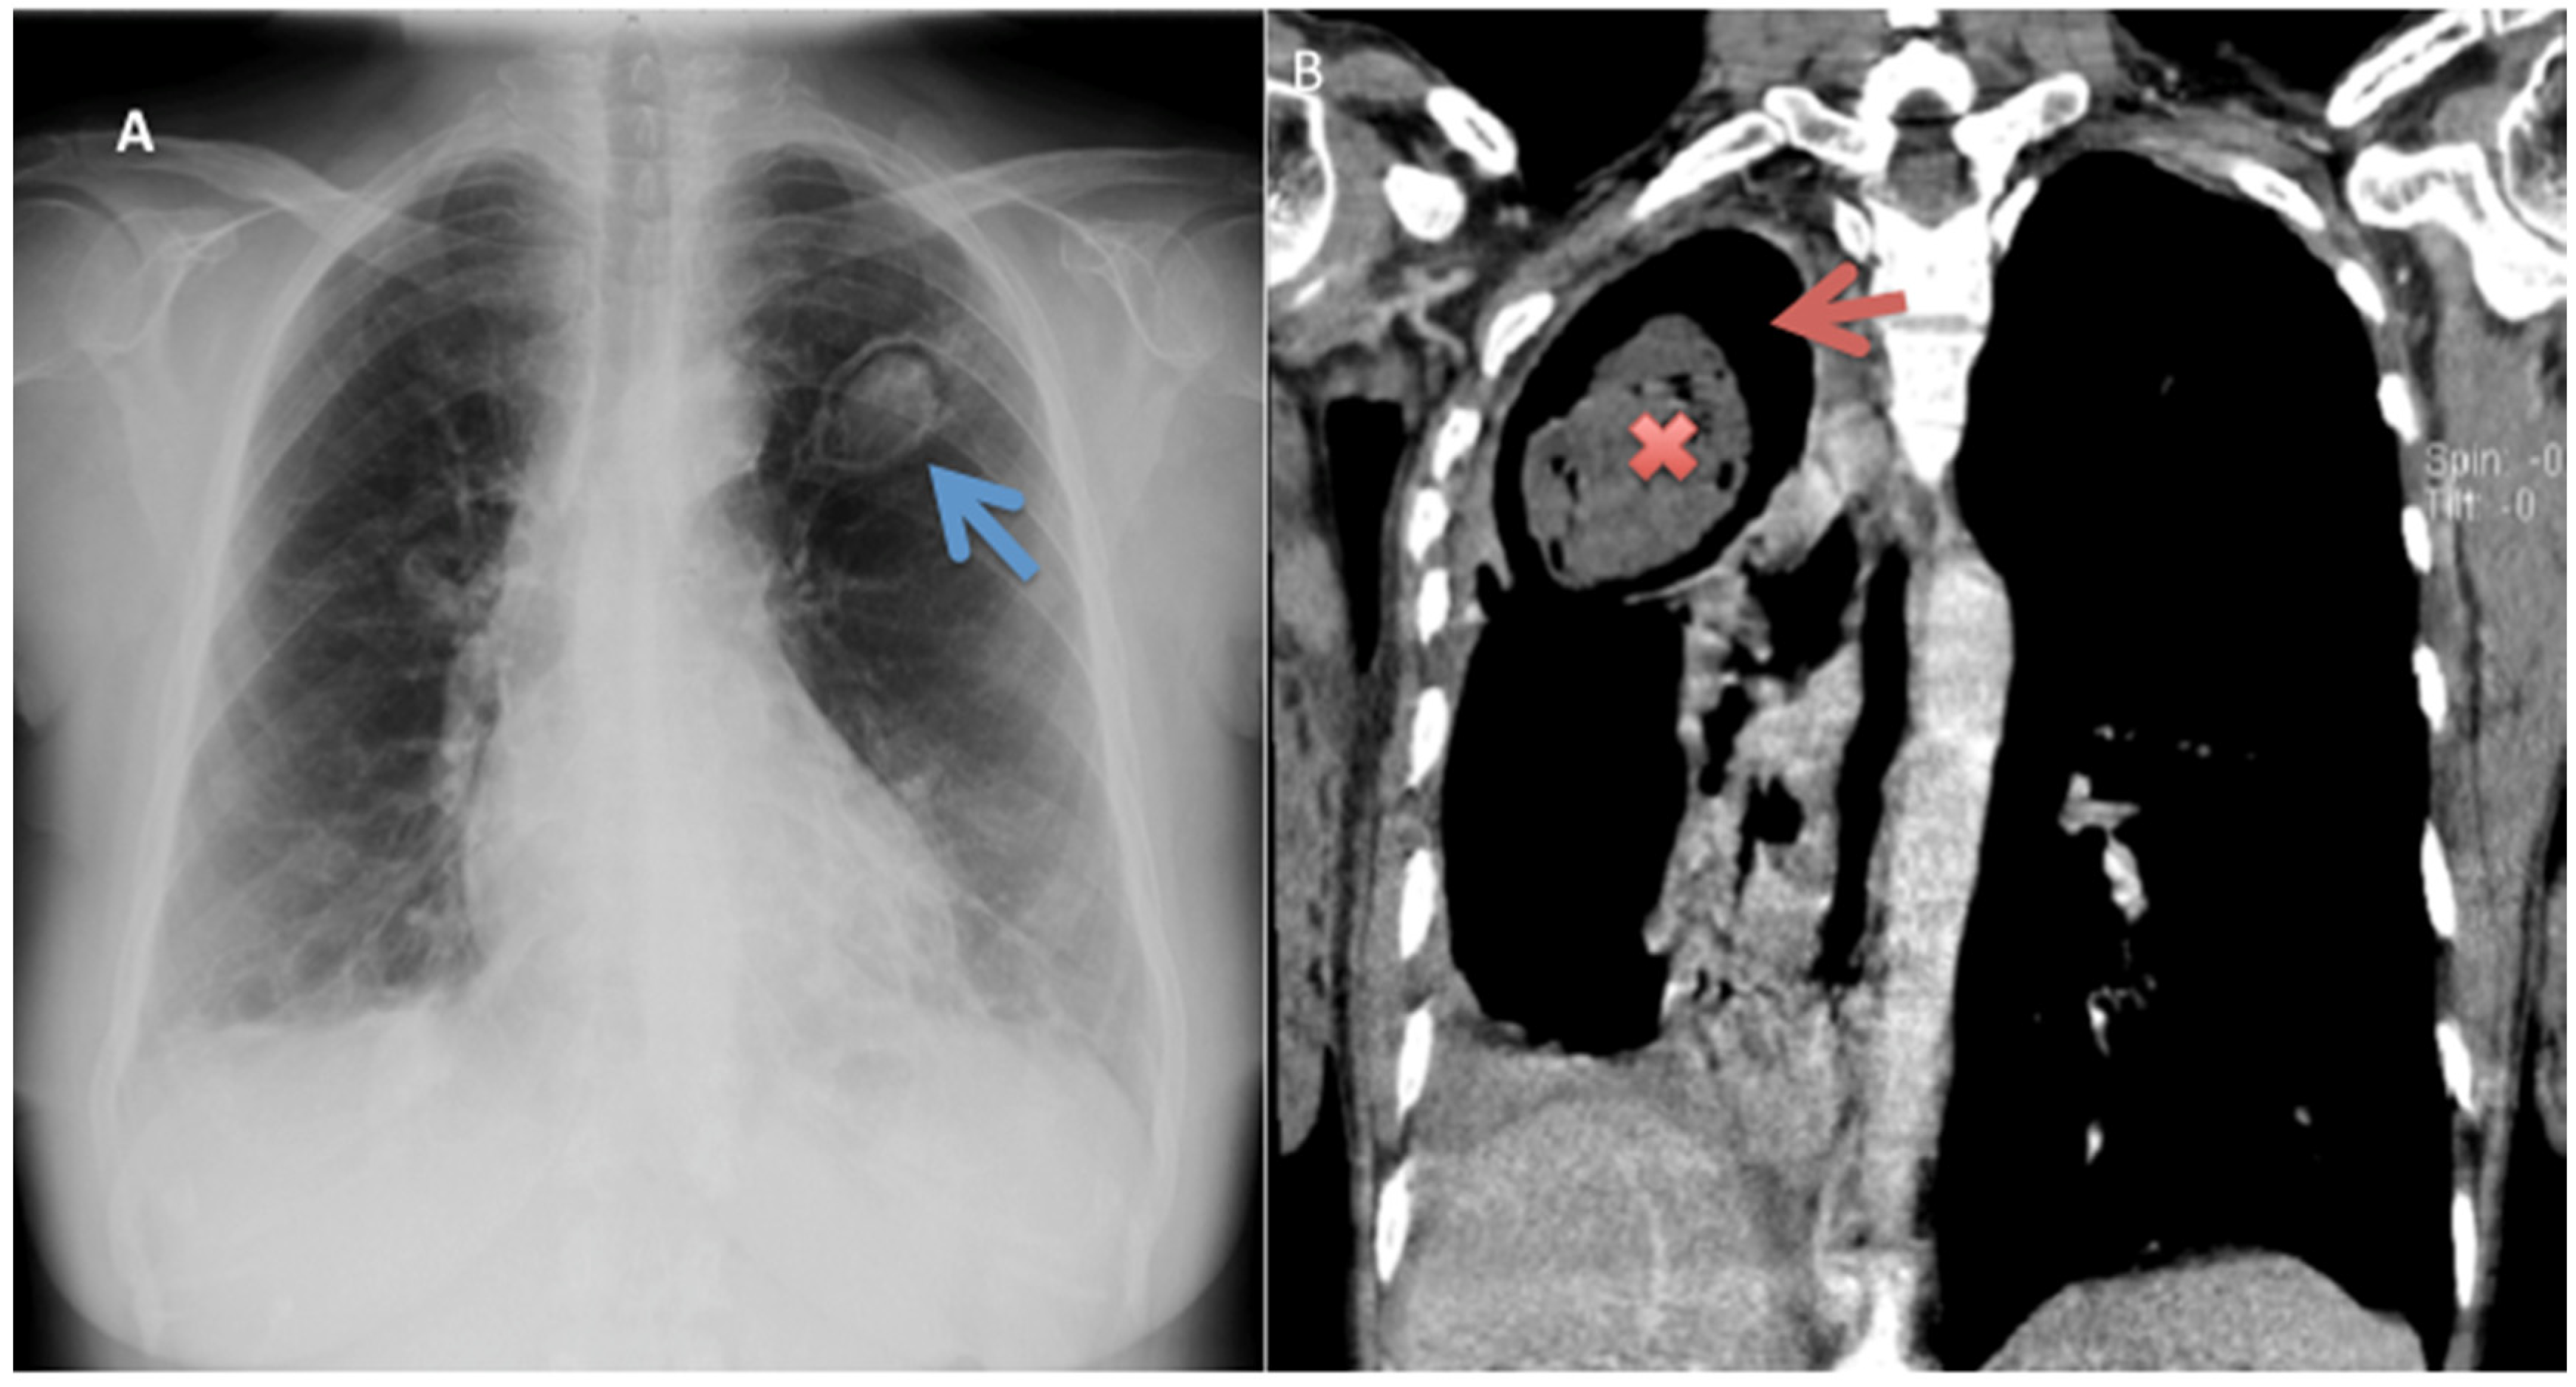

5.2. Radiology

- Desai, S.R.; Hedayati, V.; Patel, K.; Hansell, D.M. Chronic Aspergillosis of the Lungs: Unravelling the Terminology and Radiology. Eur. Radiol. 2015, 25, 3100–3107. [Google Scholar] [CrossRef]